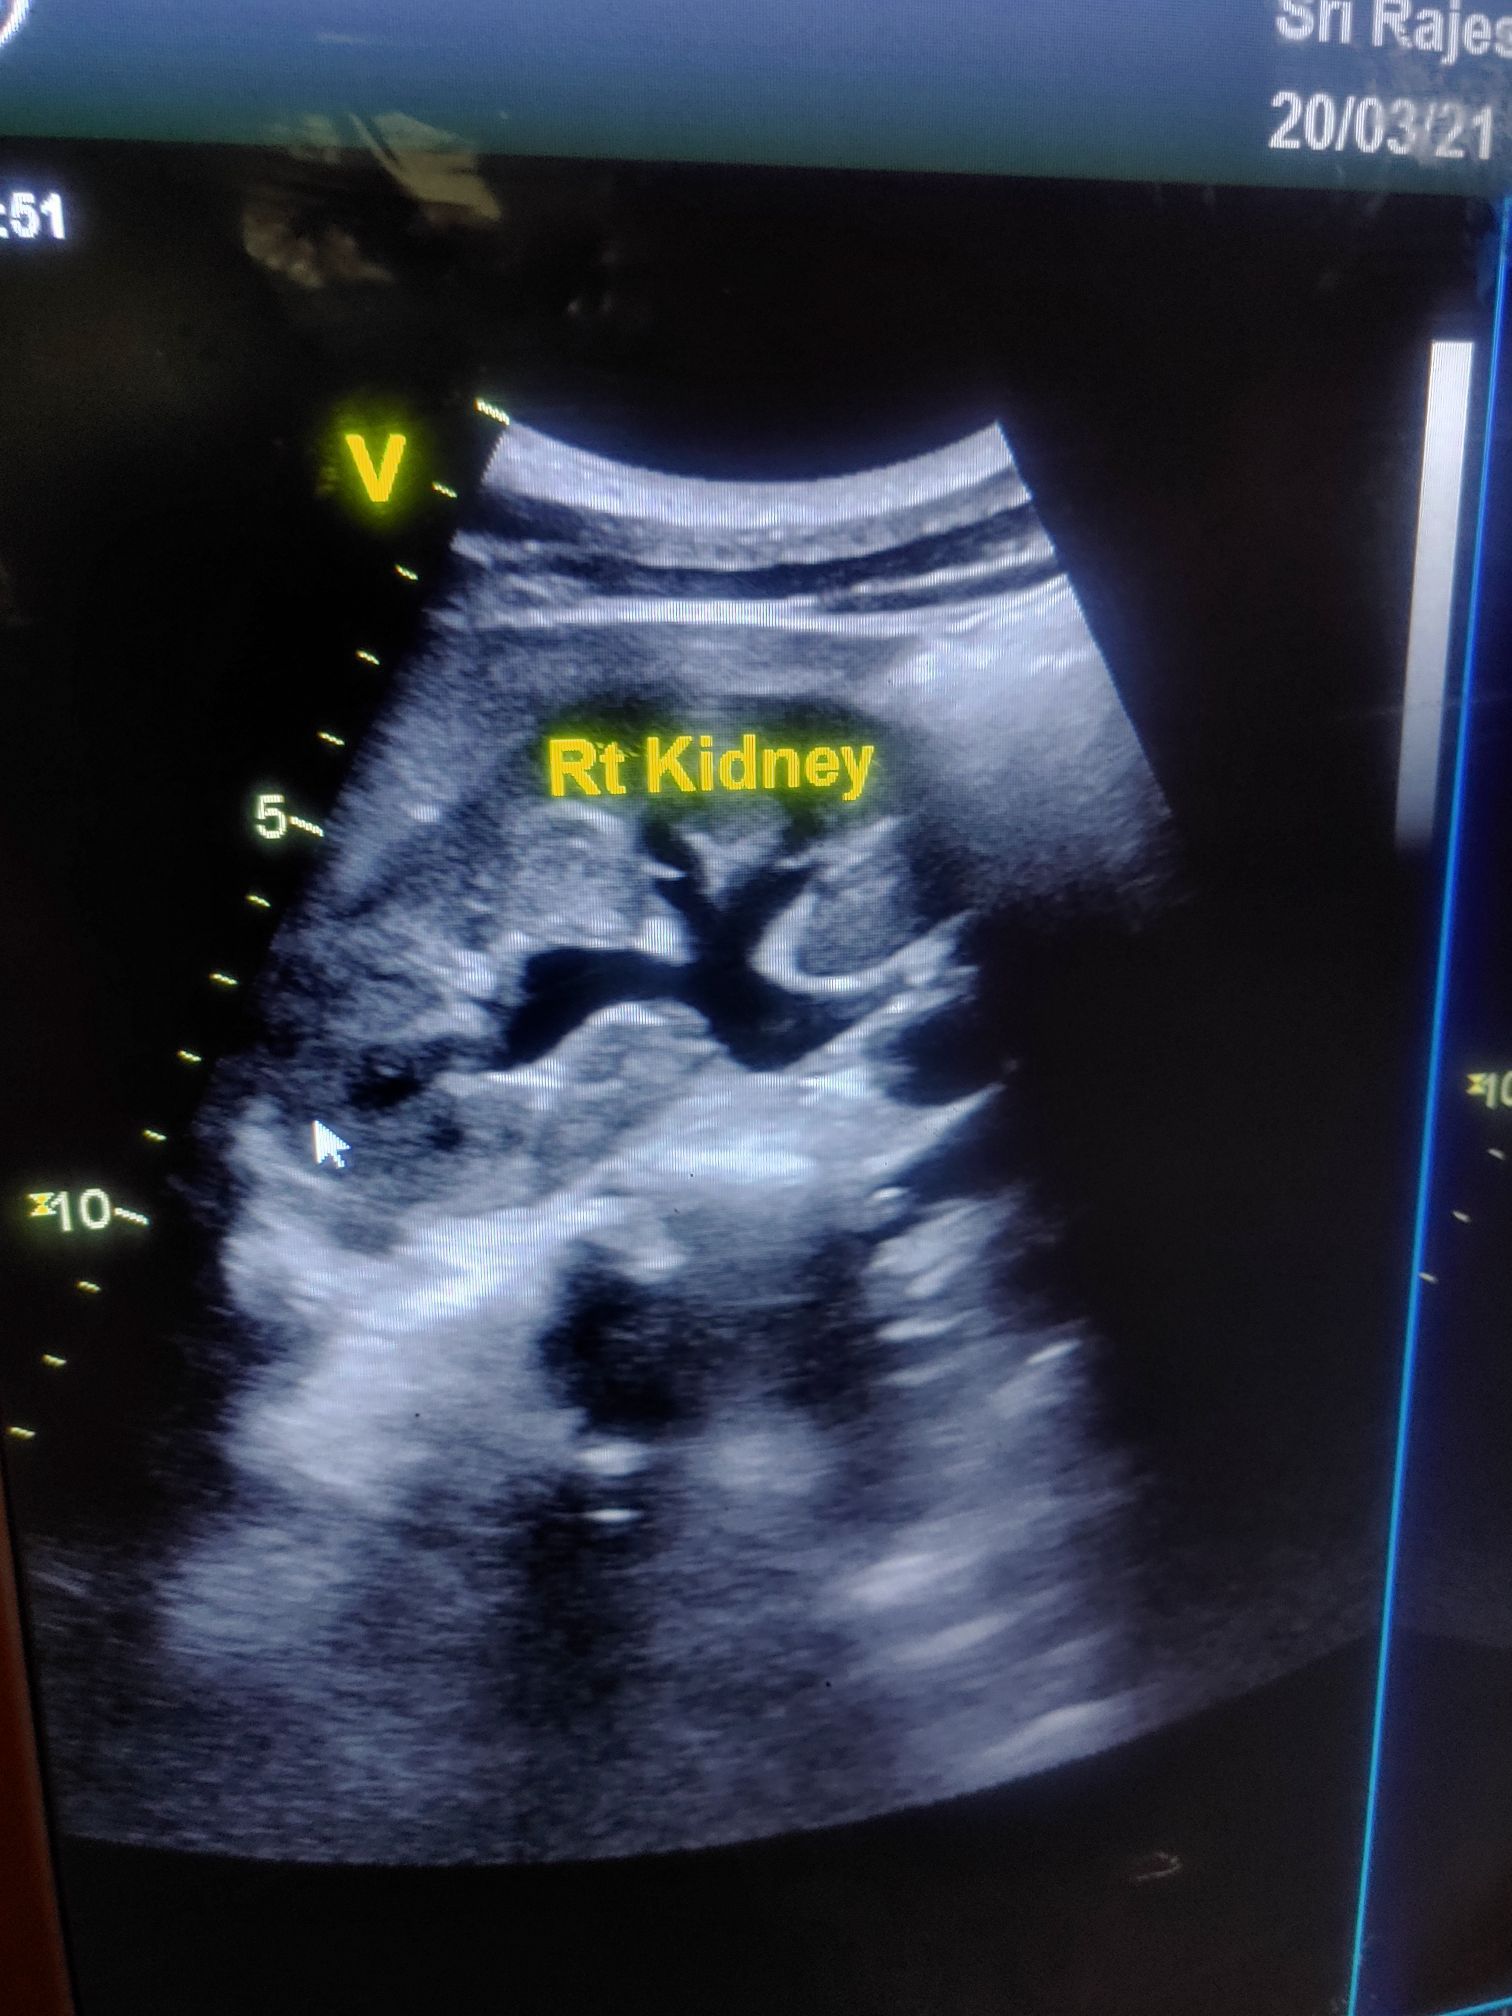

What do you think this ultrasoundπππ»π»π»π»

Grade 4 hydronephrosis?

No